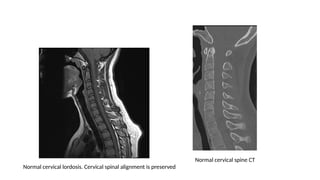

Imaging cont…

MRI

Normal cervical lordosis. Cervical spinal alignment is preserved

Normal cervical spine CT